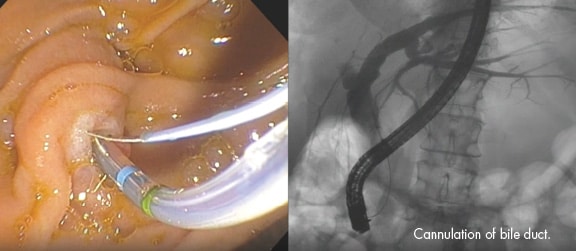

CPRE é um procedimento endoscópico que combina o uso de endoscopia e raios-x através de fluoroscopia Sua utilidade é para fins diagnósticos e terapêuticos das doenças envolvendo o pâncreas e as vias biliares, comumente associadas à obstrução da saída de bile e frequentemente associada à icterícia, que é caracterizada pela coloração amarelada da pele e dos olhosAntes do procedimento, o paciente recebe anestesia na garganta e é sedado para que não sinta nada. Após a sedação, o médico endoscopista introduz o aparelho de CPRE passando pela boca, esôfago, estômago e duodeno até que se encontre em frente à papila duodenal. Já posicionado de frente à papila, o objetivo é inserir um acessório especial para canular o ducto desejado, seja o ducto biliar ou o pancreático. Após o sucesso em canular, é injetado contraste e visualizado sob raios-x para correta localização da obstrução. Na etapa seguinte, procede-se ao corte da papila (papilotomia) para poder finalizar o procedimento com a retirada de cálculos ou com a colocação de uma prótese.